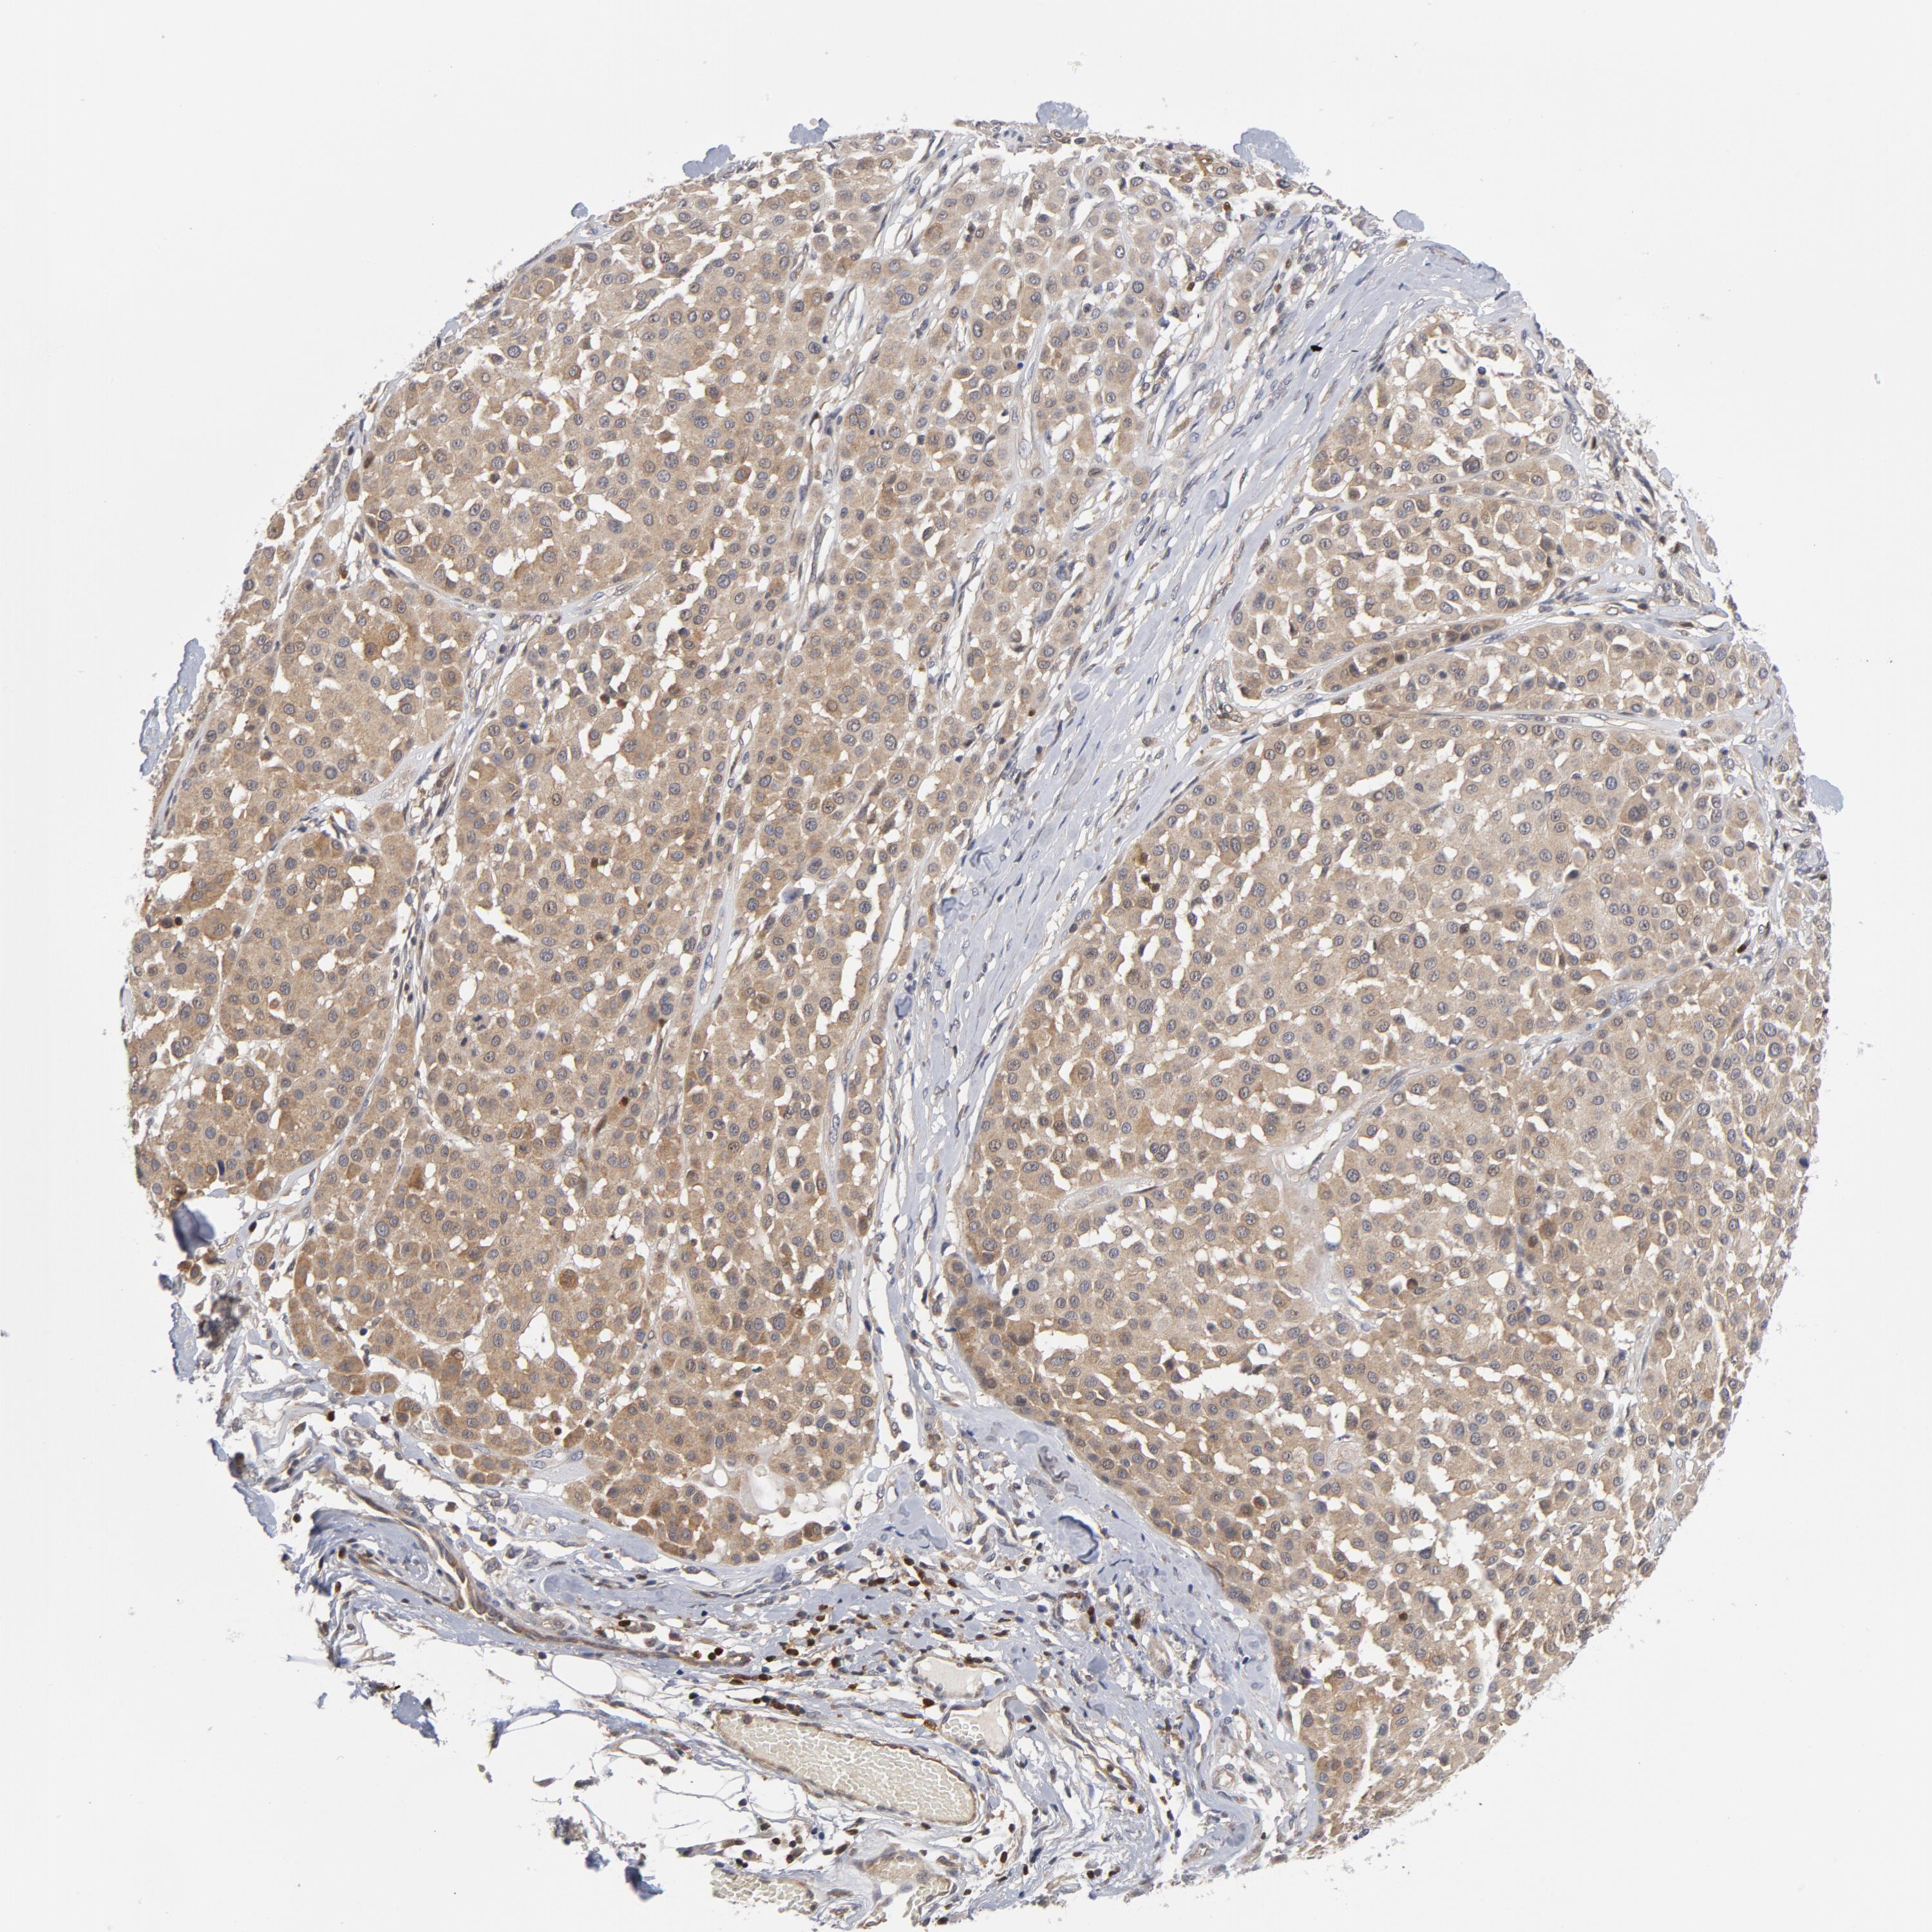

MELANOMA - Protein expressioni

A mouse-over function shows sample information and annotation data. Click on an image to view it in a full screen mode. Samples can be filtered based on level of antibody staining by selecting one or several of the following categories: high, medium, low and not detected. The assay and annotation is described here.

Antibody stainingi

Antibody staining in the annotated cell types in the current human tissue is reported as not detected, low, medium, or high, based on conventional immunohistochemistry profiling in selected tissues. This score is based on the combination of the staining intensity and fraction of stained cells.

Each image is clickable and will lead to virtual microscopy that enables deeper exploration of all samples and also displays staining intensity scores, fraction scores and subcellular localization as well as patient and tissue information for each sample.

Antibody HPA071341

Antibody CAB004602

Staining

High

Medium

Low

Not detected

Intensity

Strong

Moderate

Weak

Negative

Quantity

>75%

75%-25%

<25%

None

Location

Nuclear

Cytoplasmic/membranous

Cytoplasmic/membranous,nuclear

Malignant melanoma, NOS

Malignant melanoma, Metastatic site